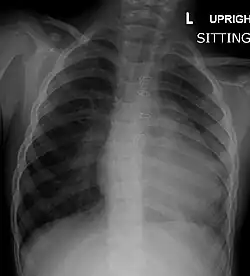

A chest X-ray of a child with tetralogy of Fallot

There are three different useful diagnostic tests used for the diagnosis of tetralogy of Fallot.[49] These include a chest radiograph, electrocardiogram, and echocardiogram.[49] The echocardiography determines the final diagnosis and typically offers enough information for surgical treatment planning.[49] About half of all patients are now diagnosed before they are born.[49] Differential diagnosis is when physicians diagnose between two or more conditions for a person's symptoms and this can include primary pulmonary causes of cyanosis, cyanotic heart lesions, pulmonary stenosis and transposed arterial trunks.[49]

Chest radiograph

Before more sophisticated techniques became available, chest X-ray was the definitive method of diagnosis. The abnormal "coeur-en-sabot" (boot-like) appearance of a heart with tetralogy of Fallot is classically visible via chest X-ray, although most infants with tetralogy may not show this finding.[50] The boot like shape is due to the right ventricular hypertrophy present in TOF. Lung fields are often dark (absence of interstitial lung markings) due to decreased pulmonary blood flow.[51]: 171–172